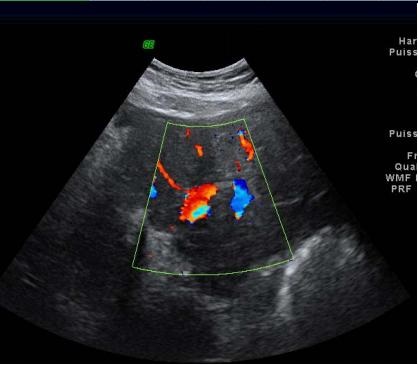

Image echographique Doppler

en couleur d'une steatose du foie marquee: Aspect de

distortion vasculaire intrahepatique |

Steatose du foie marque :

Amortissement du flux sanguine intra-hepatique |